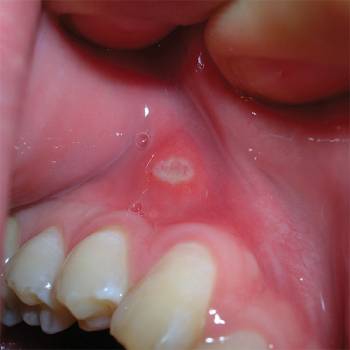

Blemmer er normalt runde sår med en diameter på 5-10 mm, men de kan være større eller mindre. Såret er typisk gulhvit og omringet av en rød, litt forhøyet kant. Sårene er ofte smertefulle og kan være veldig irriterende, både ved å snakke, spising og tannpussing. Blemmer oppstår typisk på innsiden av leppene, på munnen og slimhinnen samt tungen. Blemmer er en tilstand som kommer og går - et utbrudd varer normalt 7-14 dager.

blemmer på munnslimhinnen

Blemme på munnslimhinnen i overkjeven.